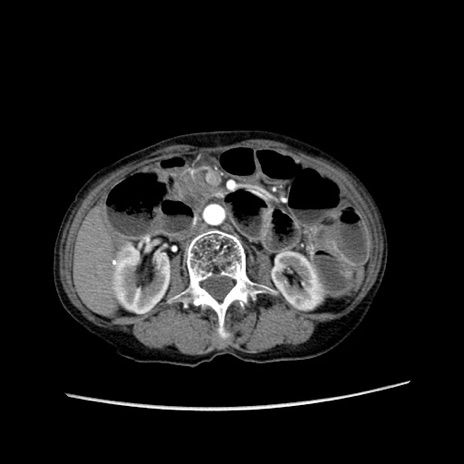

症例25(横断像)

【症例】80歳代女性

【主訴】胸のつかえ感

【現病歴】約9時間前に食後から胸のつかえた感じあり、嘔吐あり、来院。

【既往歴】胃癌(全摘)、胆摘、虫垂炎

【身体所見】心窩部に圧痛あり、反跳痛なし。

【データ】WBC 5700、CRP 0.05